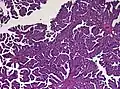

Histopathology

The tumor is neuroectodermal in origin and similar in structure to a normal choroid plexus. They may be created by epithelial cells of the choroid plexus. Papillary fronds lined by bland columnar epithelium are visible under the microscope. Normal absences include mitotic activity, nuclear pleomorphism, and necrosis.[10] Tumors have positive immunohistochemistry for cytokeratin, vimentin, podoplanin, and S-100.[11] Up to 20% of choroid plexus papilloma patients may test positive for glial fibrillary acidic protein (GFAP).[12] Studies have found that fourth ventricle cancers express more S100 than lateral ventricle tumors, and older patients (over 20 years) express more GFAP and transthyretin than younger patients.[13] Some individuals with choroid plexus papilloma have germline TP53 gene mutations, according to genetic analyses.[14] These cancers rarely exhibit nuclear p53 protein positivity. Aicardi syndrome, hypomelanosis of Ito, and 9p duplication are syndromic correlations of choroid plexus papilloma.

Micrograph of a choroid plexus papilloma. H&E stain. -